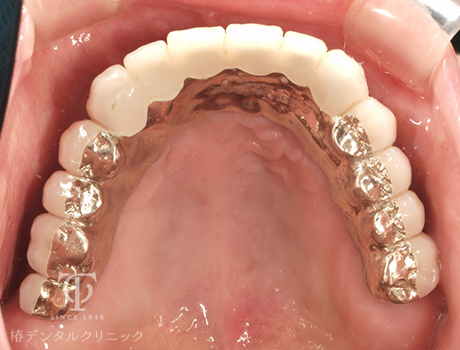

術後の上顎内冠

術後の上顎AGCテレスコープ義歯

正面観AGCテレスコープ義歯装着

- 症状

- 右上の痛み

- 治療期間

- 約1年半

- 治療費用

- (上顎)インプラント治療:473,000円×2

(上顎)AGCテレスコープ義歯:1,500,000円

(下顎)インプラント治療:473,000円×2

右上の歯が痛いということで来院されました。インプラントとAGCテレスコープという方法でかみ合わせを再構築しました。

【リスク・副作用】

インプラント治療後、痛みや違和感、出血、腫れなどが出る事があります。喫煙者、糖尿病などの方の場合、歯が生着しない場合があります。入れ歯を清潔に保たないと虫歯や歯肉炎、歯周病になるリスクがあります。